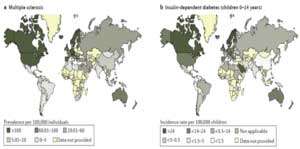

One out of two Americans suffer from immune disorders. If we look attentively at the changes occurring in our environment, we will notice some trends running in parallel: an exponential increase in chronic diseases, a similarly exponential trend of increasing strain on our immune system, but also an exponential increase in organic nutritional and behavioral concepts (Figure 1 and Figure 2).

Chronic diseases, such as cancer, ALS, Alzheimer’s disease, Parkinson’s disease, MS, Crohn’s disease and chronic fatigue syndrome, Breast Cancer are increasing at an explosive rate, and extrapolation of the curves shows that within a few years, everyone living in the Western world will be affected by at least one of these diseases.

A change in mindset is urgently required, as there are unfortunately certain factors in our environment that pose a progressively intensive risk to our health: increasing electromagnetic radiation in the form of high gigahertz frequencies related to mobile communications, WLAN and DECT technology. Also, the addition of titanium oxide (E171) to cosmetics, sun screen, oral contraceptives, toothpaste, chewing gum and even yogurt has led to an increasing intolerance to titanium, which is still being used in alternative medicine and traumatology. Yet even in its purest form ‘Grade 1 titanium’, this chemical element still contains up to 0.20 % iron and traces of nickel as well. This is an alarming fact when you consider that 80% of women in Europe experience an allergic reaction to nickel. More significant risk factors present the intraoral interference fields.